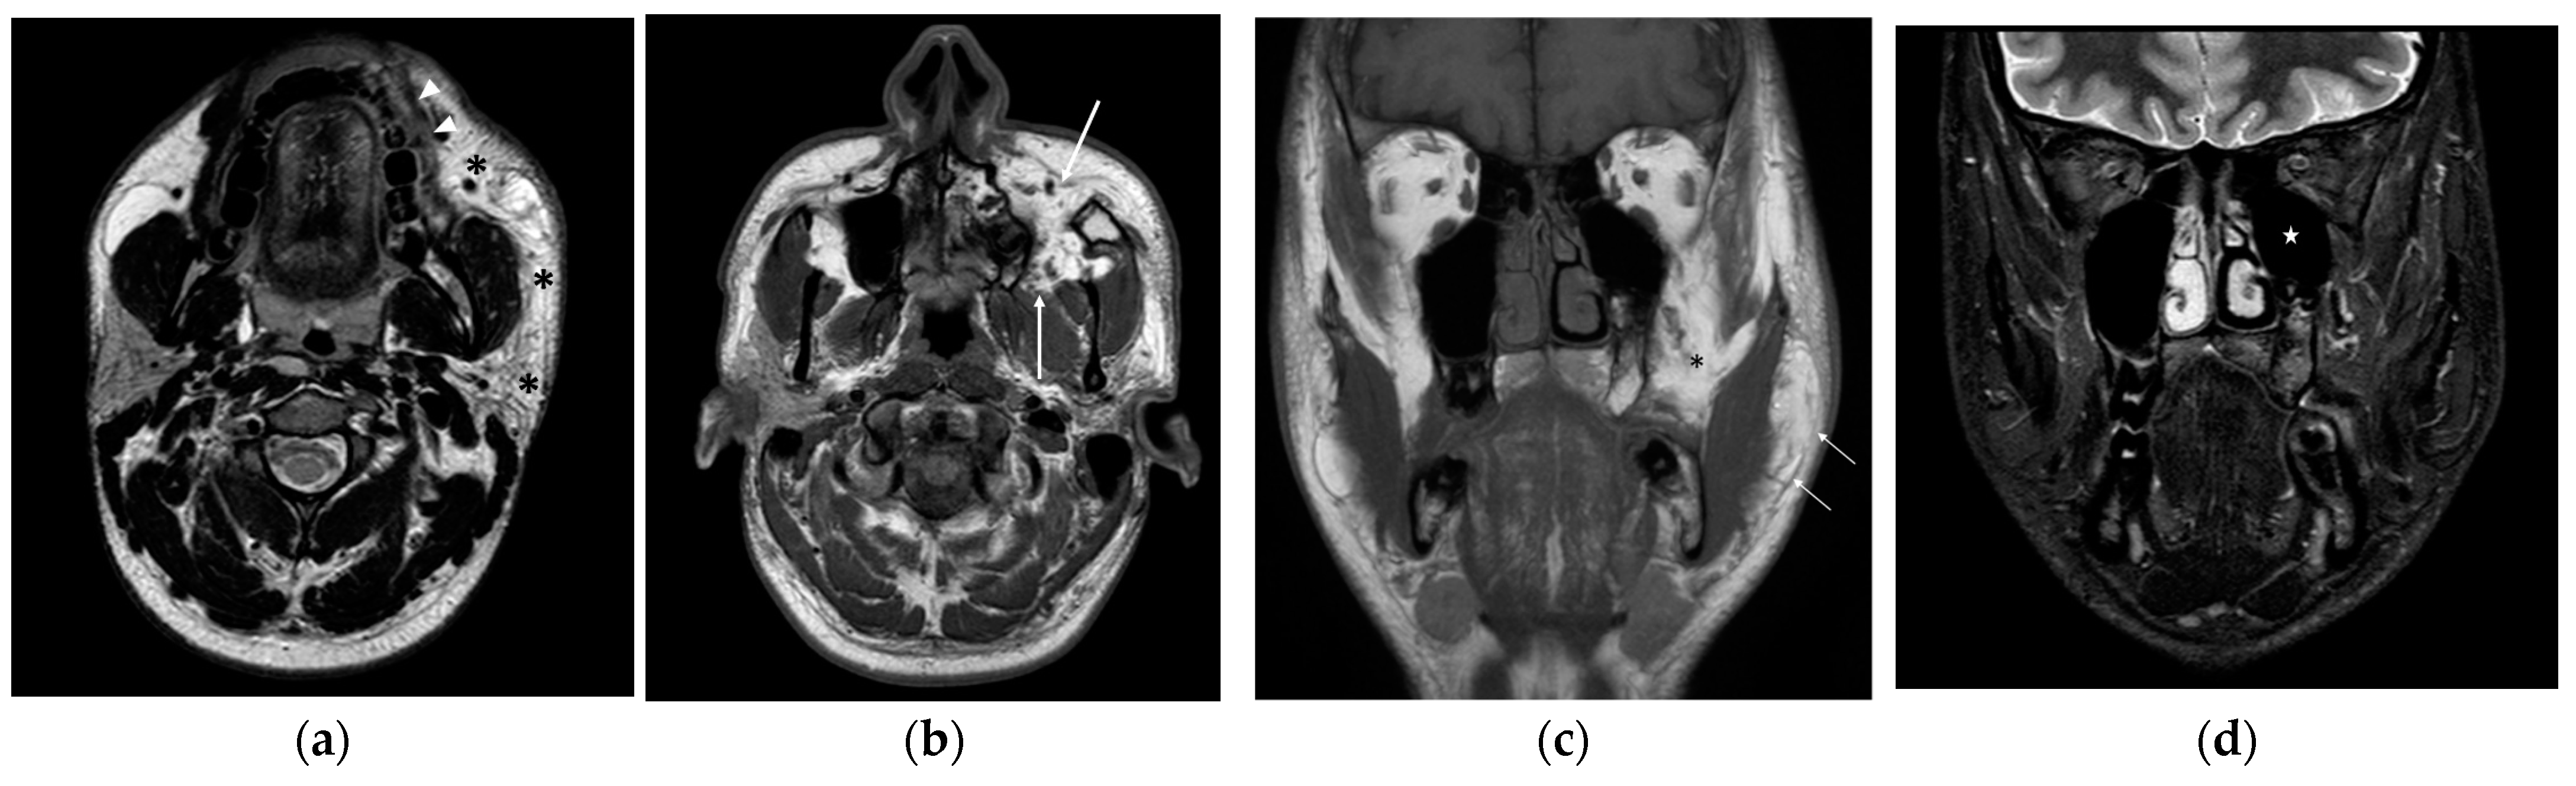

Figure 2.

Axial T2-weighted Turbo spin echo scan (a) shows a non-capsulated lipomatous lesion, extending into the buccal, masticatory, and parotid spaces of the left hemiface (asterisks) with infiltration of the left orbicularis oris muscle (arrowheads). Axial T1-weighted turbo spin echo image (b) also demonstrates the deep extension of the lesion into the infratemporal fossa and pterygomandibular space (spaces between arrows). Coronal T1-weighted turbo spin echo scan (c) displays fat hypertrophy within the left hemiface (arrows) and the pterygomandibular space (asterisk). On coronal T2-weighted spectral presaturation with inversion recovery scan (d) hypoplasia of the ipsilateral maxillary sinus (star) is also detectable.